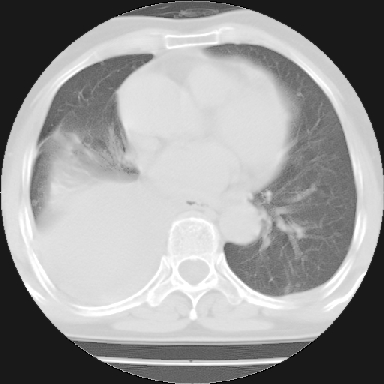

以下是引用苯小孩在2007-4-13 16:20:00的发言:[br]1、右下肺中央型肺癌并阻塞性肺不张、肺内转移、胸椎右侧附件亦有转移<横断层面第8层>.[br]2、右侧胸腔积液.

以下是引用swyyy2007在2007-4-13 15:31:00的发言:[br]右肺门下区肿块,右肺下叶支气管阻塞,右肺下叶不张,右侧大量胸腔积液,右肺中叶见结节状高密度影,边缘清,纵隔内见肿大淋巴结。首先考虑右下肺中心型肺癌伴右肺下叶不张、中叶、纵隔淋巴结转移。右侧胸腔积液。